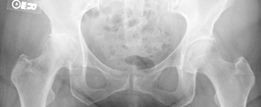

Demographics Age : 33 years Sex : female BMI : 24 Relevant Past Medical History Principal pathologies : Resid…